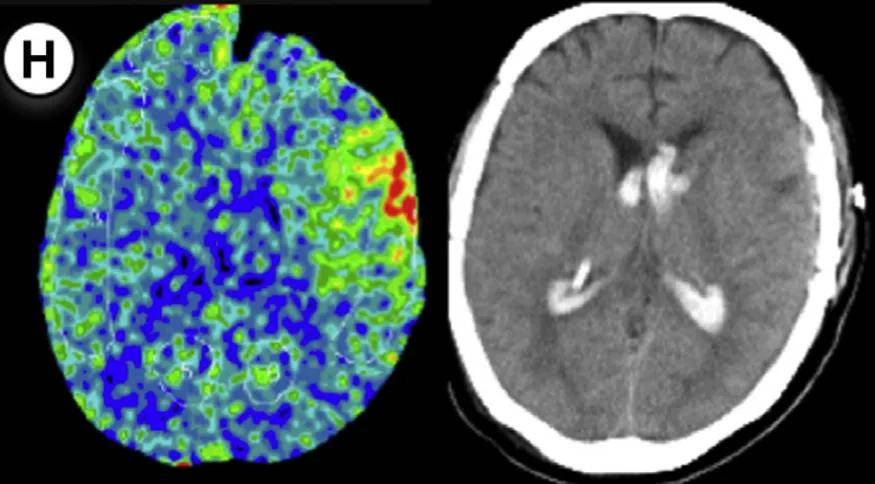

研究团队发现,术后即时监测的局部脑血流(rCBF)增加率是预测出血的关键指标。主要采用两种计算方法:

方法1(横向比较):手术侧rCBF值除以非手术侧rCBF值

方法2(纵向比较):术后手术侧rCBF值除以术前手术侧rCBF值

当rCBF增加率超过特定阈值(方法1≥30%,方法2≥50%)时,出血风险显著增加。以下七个病例验证这一规律:

通过氙气增强CT,在大脑中动脉供血区固定部位测量rCBF,术后即时完成首次检测。